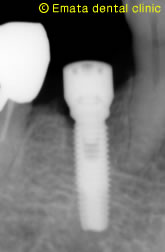

重要なのはインプラントをいれる位置です。抜歯した部位にいれると外側の骨はなくなってしまします。抜歯した部位より内側にはいっているのがわかりますか?

インプラントと抜歯間に少し隙間があきますが、最新の知見ではその隙間に吸収しづらい人工骨を入れることが推奨されています。

初期固定(インプラント治療で一番重要です)がとてもよかったのでキャップをつけて1回法でおこないました。

術後のレントゲン